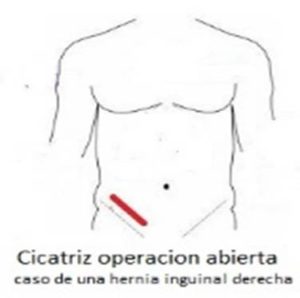

La cirugía de la hernia inguinal, desde el origen de su tratamiento quirúrgico a finales del siglo XIX y durante todo el siglo XX, se ha realizado accediendo a la región inguinal por delante, es decir, incidiendo la piel en la misma región inguinal donde abulta la hernia y se va profundizando hasta llegar al defecto herniario que se repara por esta vía. Es lo que se llama cirugía abierta o por vía anterior de la hernia inguinal.

- En la cirugía abierta por lo general, la duración de la operación es algo menor y el gasto sanitario es también algo más reducido. Este tipo de consideraciones son importantes en la gestión sanitaria, especialmente donde la presión asistencial es enorme como ocurre en la sanidad pública.

Como se ha dicho, la cirugía tradicional de la hernia por vía anterior conlleva una larga convalecencia debido al dolor postoperatorio que exige, para su tratamiento, además del consumo de analgésicos, un nivel de reposo considerable, a veces incluso absoluto, que casi siempre se extiende entre 1 o 2 meses. En algunas ocasiones incluso alguna semana más para recuperarse plenamente.

Como se ha dicho, la cirugía tradicional de la hernia por vía anterior conlleva una larga convalecencia debido al dolor postoperatorio que exige, para su tratamiento, además del consumo de analgésicos, un nivel de reposo considerable, a veces incluso absoluto, que casi siempre se extiende entre 1 o 2 meses. En algunas ocasiones incluso alguna semana más para recuperarse plenamente.

Consecuencia de lo cual, retrasa considerablemente la incorporación del paciente a su actividad laboral o actividad física rutinaria.

Consecuencia de lo cual, retrasa considerablemente la incorporación del paciente a su actividad laboral o actividad física rutinaria.